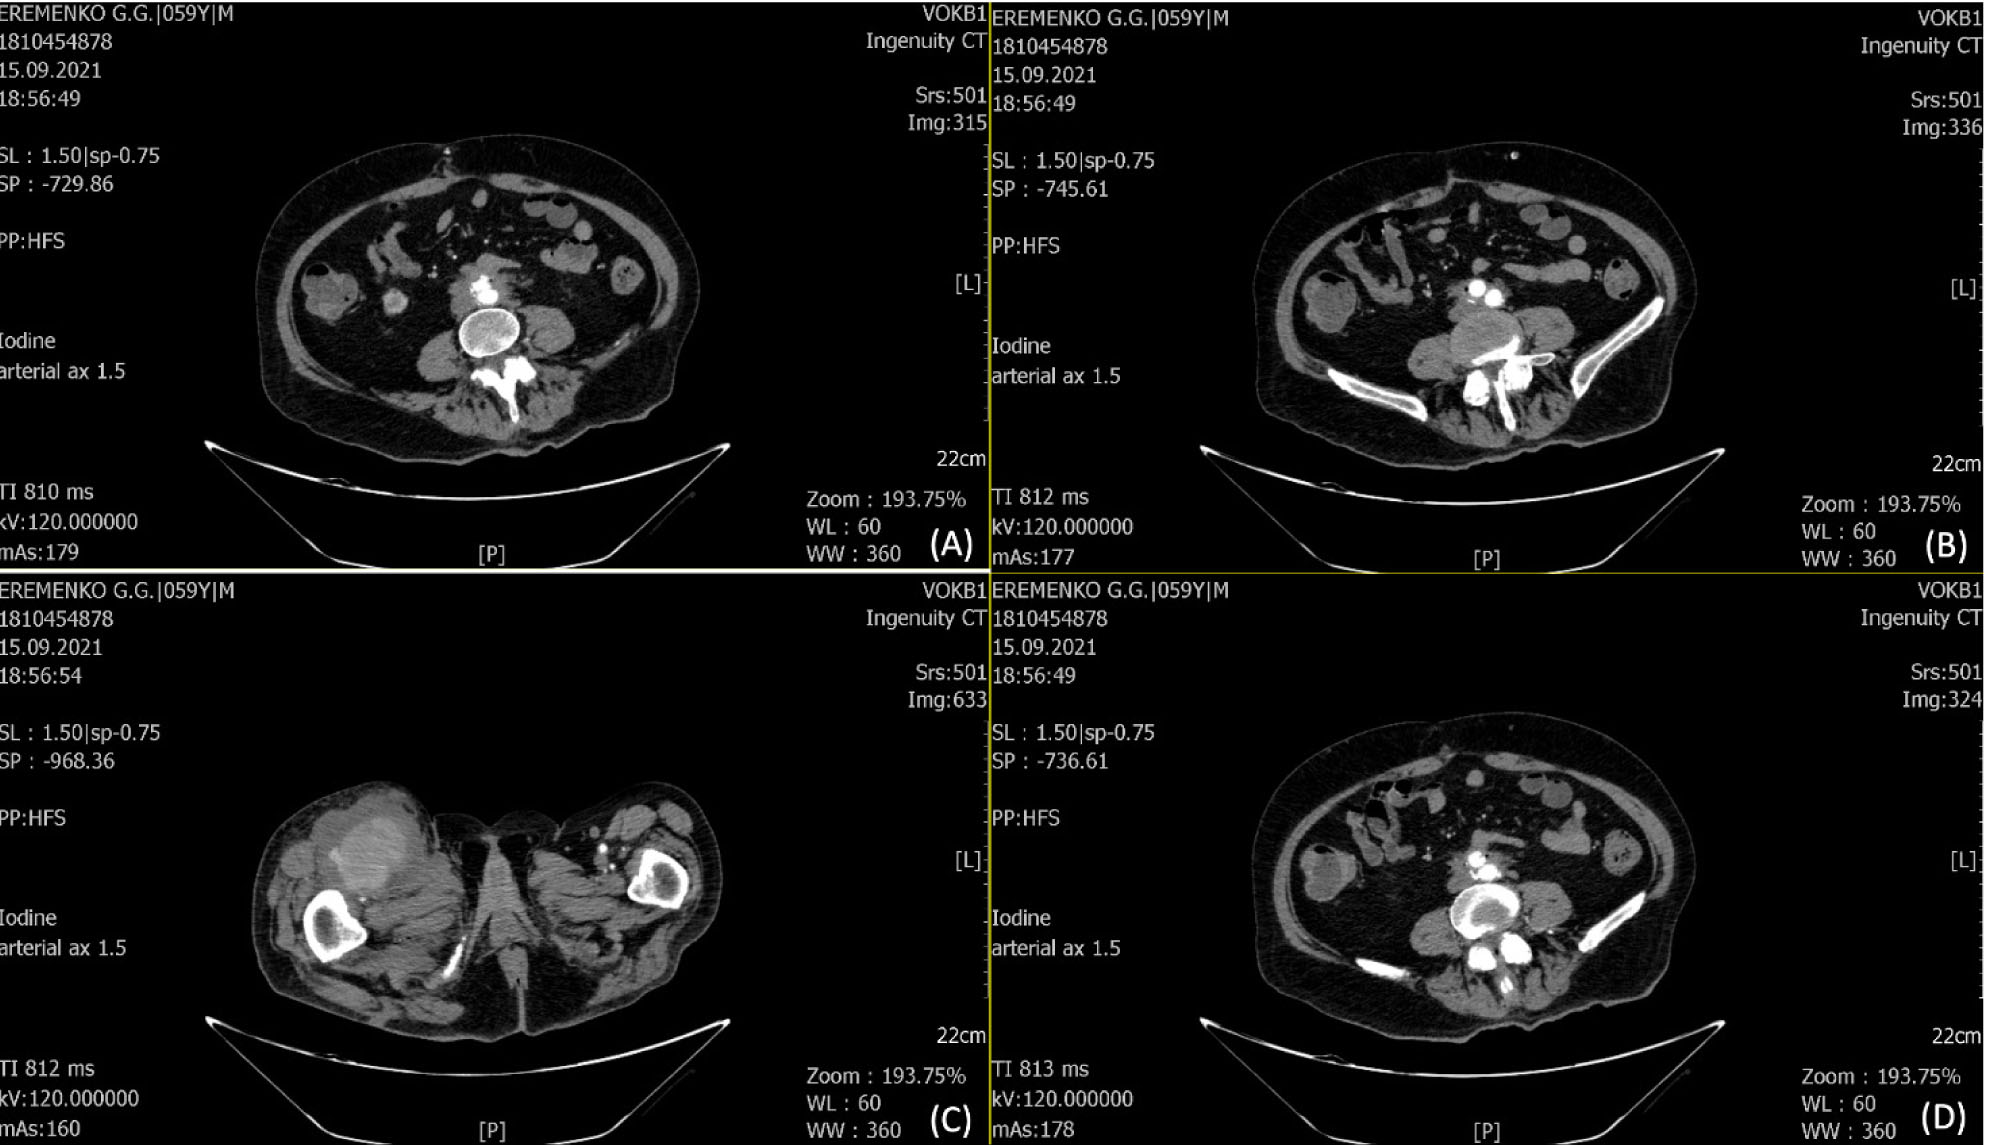

Пациент в возрасте 60 лет в 2016 г. после резекции аневризмы инфраренального отдела аорты с внутримешковым аорто-подвздошным протезированием справа, аорто-бедренным протезированием слева в другом лечебном учреждении. Поступил в нашу клинику в сентябре 2021 года с жалобами на наличие пульсирующего мешотчатого образования в области верхней трети правого бедра, подъем температуры до 37,5–40,1 °С в течение двух недель. Операции в анамнезе: вскрытие абсцесса правой голени от июля 2020 г., вскрытие абсцесса и флегмоны правой нижней конечности от января 2021 г., холецистэктомия от января 2021 г. Операции выполнялись в других лечебных учреждениях. Выполнено ультразвуковое исследование (УЗИ) мягких тканей правого бедра: в верхней трети и средней трети по внутренней поверхности бедра вдоль сосудистого пучка визуализируется гипоэхогенное образование неоднородной структуры на протяжении более 10 см толщиной от 0,6 до 1,2 см на глубине до 1,4 см аваскулярное при цветном дуплексном сканировании (ЦДК). В верхней трети бедра визуализируется шаровидной формы аневризма с d – 4,6 на протяжении 5,1 см. Инфильтрация окружающих тканей. Обращаем внимание: у пациента уже в анамнезе два глубоких гнойных очага не ясного происхождения в правой нижней конечности. На КТ ангиографии брюшной аорты и подвздошных сосудов – псевдоаневризма с формирующимся абсцессом (рис. 2).

Рис. 2. КТА брюшной аорты и подвздошных сосудов – картина, характерная для ложной аневризмы с деструктивными воспалительными изменениями окружающей клетчатки (формирующийся абсцесс) (C). Не исключается парааортальный воспалительный процесс на уровне бифуркации за счет пакета увеличенных лимфатических узлов (A, B, D). Субокклюзия глубокой и поверхностной бедренных артерий справа